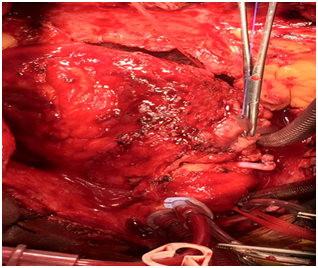

Surgical intervention was done with cardiopulmonary bypass. After Sternotomy, severe dense pericardial adhesion had been seen around the pseudoaneurysdm , adhesion was very carefully dissected, pseudoaneurysm was opened, palpated the stent on RCA, stent had been removed, endarterectomy was done in RCA distal to pseudoaneurysm, 2 small perforation in RCA was repaired by 6-0 polypropylene, RCA proximally and distally ligated with 4-0 polypropylene. Most of the wall of the Pseudoaneurysm had been removed and marsupialization was done. Venous graft was given to distal RCA after long endarterectomy (Figures 1–7).

Figure 2 Severe pericardial adhesions.

Figure 3 Pseudoaneurysm in right coronary artery.